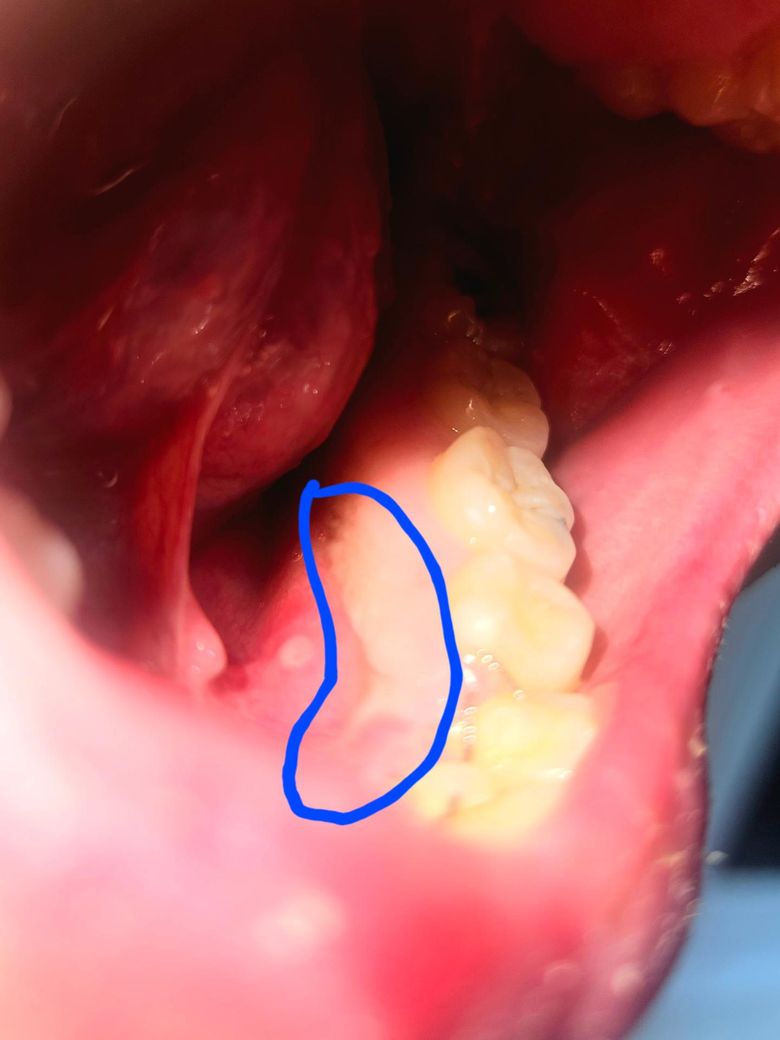

구내염이 난 자리가 크게 부은거 같아서 사진을 찍었는데, 구내염 옆으로 하얗게 경계선같은게 져있네요... 이게 뭔가요? 그리고 구내염이 꽤 딱딱하게 부어오른거 같은데, 괜찮은건지도 궁금합니다.

구내염이 심하게 생긴거 같습니다. 치과에 가셔서 저부위 소독을 받으시고 약을 바르시는게 좋을것같습니다.